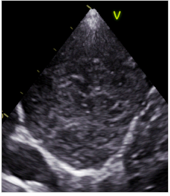

2.5. Analysis of Consolidations in Color/Power Doppler Mode

3.4. Analysis of Vascularity